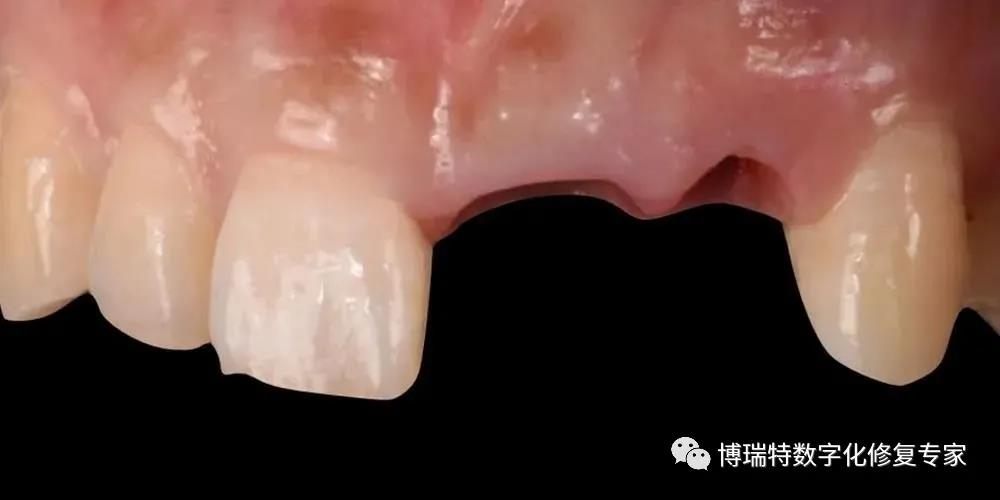

8226; 11、12一度松动,叩诊不适;

8226; 21牙冠三度松动,21牙冠冠向移位1.5mm,叩诊(+);

8226; 22冠根折,唇侧断面至龈下3mm,唇侧颈部凹陷;

8226; 高位笑线,牙龈色粉,质韧,无明显红肿;

8226; 薄龈生物型,角化龈宽度充足,龈缘高度不协调;

8226; 21龈缘根向移位约1mm;